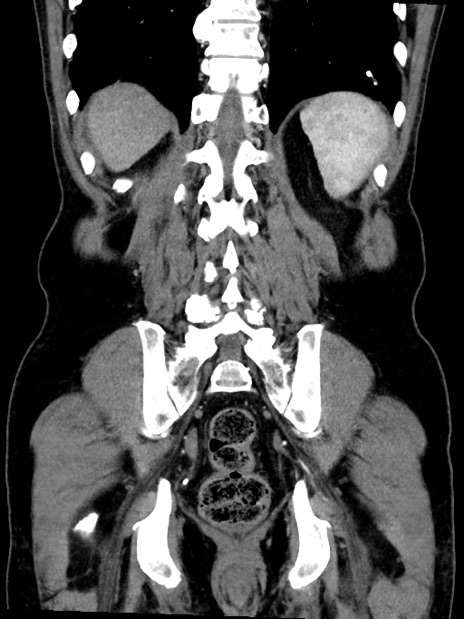

症例35(冠状断像)

【症例】70歳代 男性

【主訴】腹部膨満、嘔吐

【現病歴】昨日より腹部膨満感出現。本日増悪し、仙痛出現。嘔吐あり、受診。

【既往歴】糖尿病、胆摘後

【身体所見】BP 149/80mmHg、HR 74/min、BT 35.9℃、腹部:膨満、軟、圧痛なし。腸雑音減弱あり。上腹部正中切開瘢痕あり。

【データ】WBC 13500、CRP 1.72